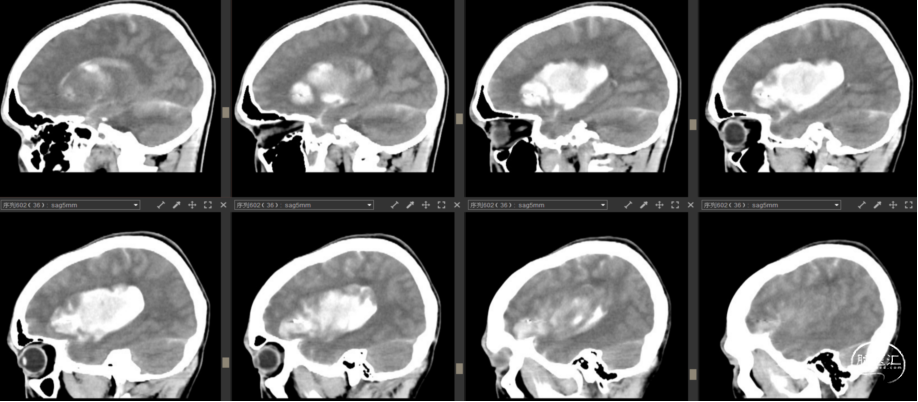

2023年7月27日

![]()

病例情况

患者梁某,女,50岁,因“右侧肢体乏力10小时余”于2023年7月27日13:29收入本区。

查体:清醒,GCS评分13分(E3V4M6),双瞳孔等圆等大,直径为2.0mm,对光反射存在,不完全性混合性失语,张口下颌无偏歪,双侧额纹对称,双侧鼻唇沟无变浅,伸舌基本居中,右上肢肌力2级,右下肢4级,左侧肌力5-级,四肢肌张力正常。

检查:2023年7月27日我院急诊头颅CT:左侧基底节脑出血,血量约14ml,出血破入脑室系统。

既往无特殊。

诊断:左侧基底节出血破入脑室

术前讨论及手术指征:考虑尽快排除脑室内积血减少脑积水发生的概率;尽快排除血肿减少血肿分泌含铁血黄素导致脑水肿。经与家属沟通,家属比较积极,行微创手术。

手术方案:经额叶入路机器人辅助导航左侧基底节血肿穿刺引流。

![]()

2023年7月27日

![]()

2023年7月28日

![]()

2023年7月30日